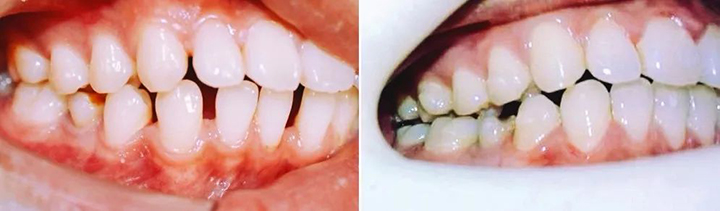

上图就是矫正前后牙齿的对比照,欢迎观看右边照片多一点!

『 排齐上下前牙,关闭前牙散在间隙 』

完整的观察一下目前达到的矫治效果,会发现真的很棒!